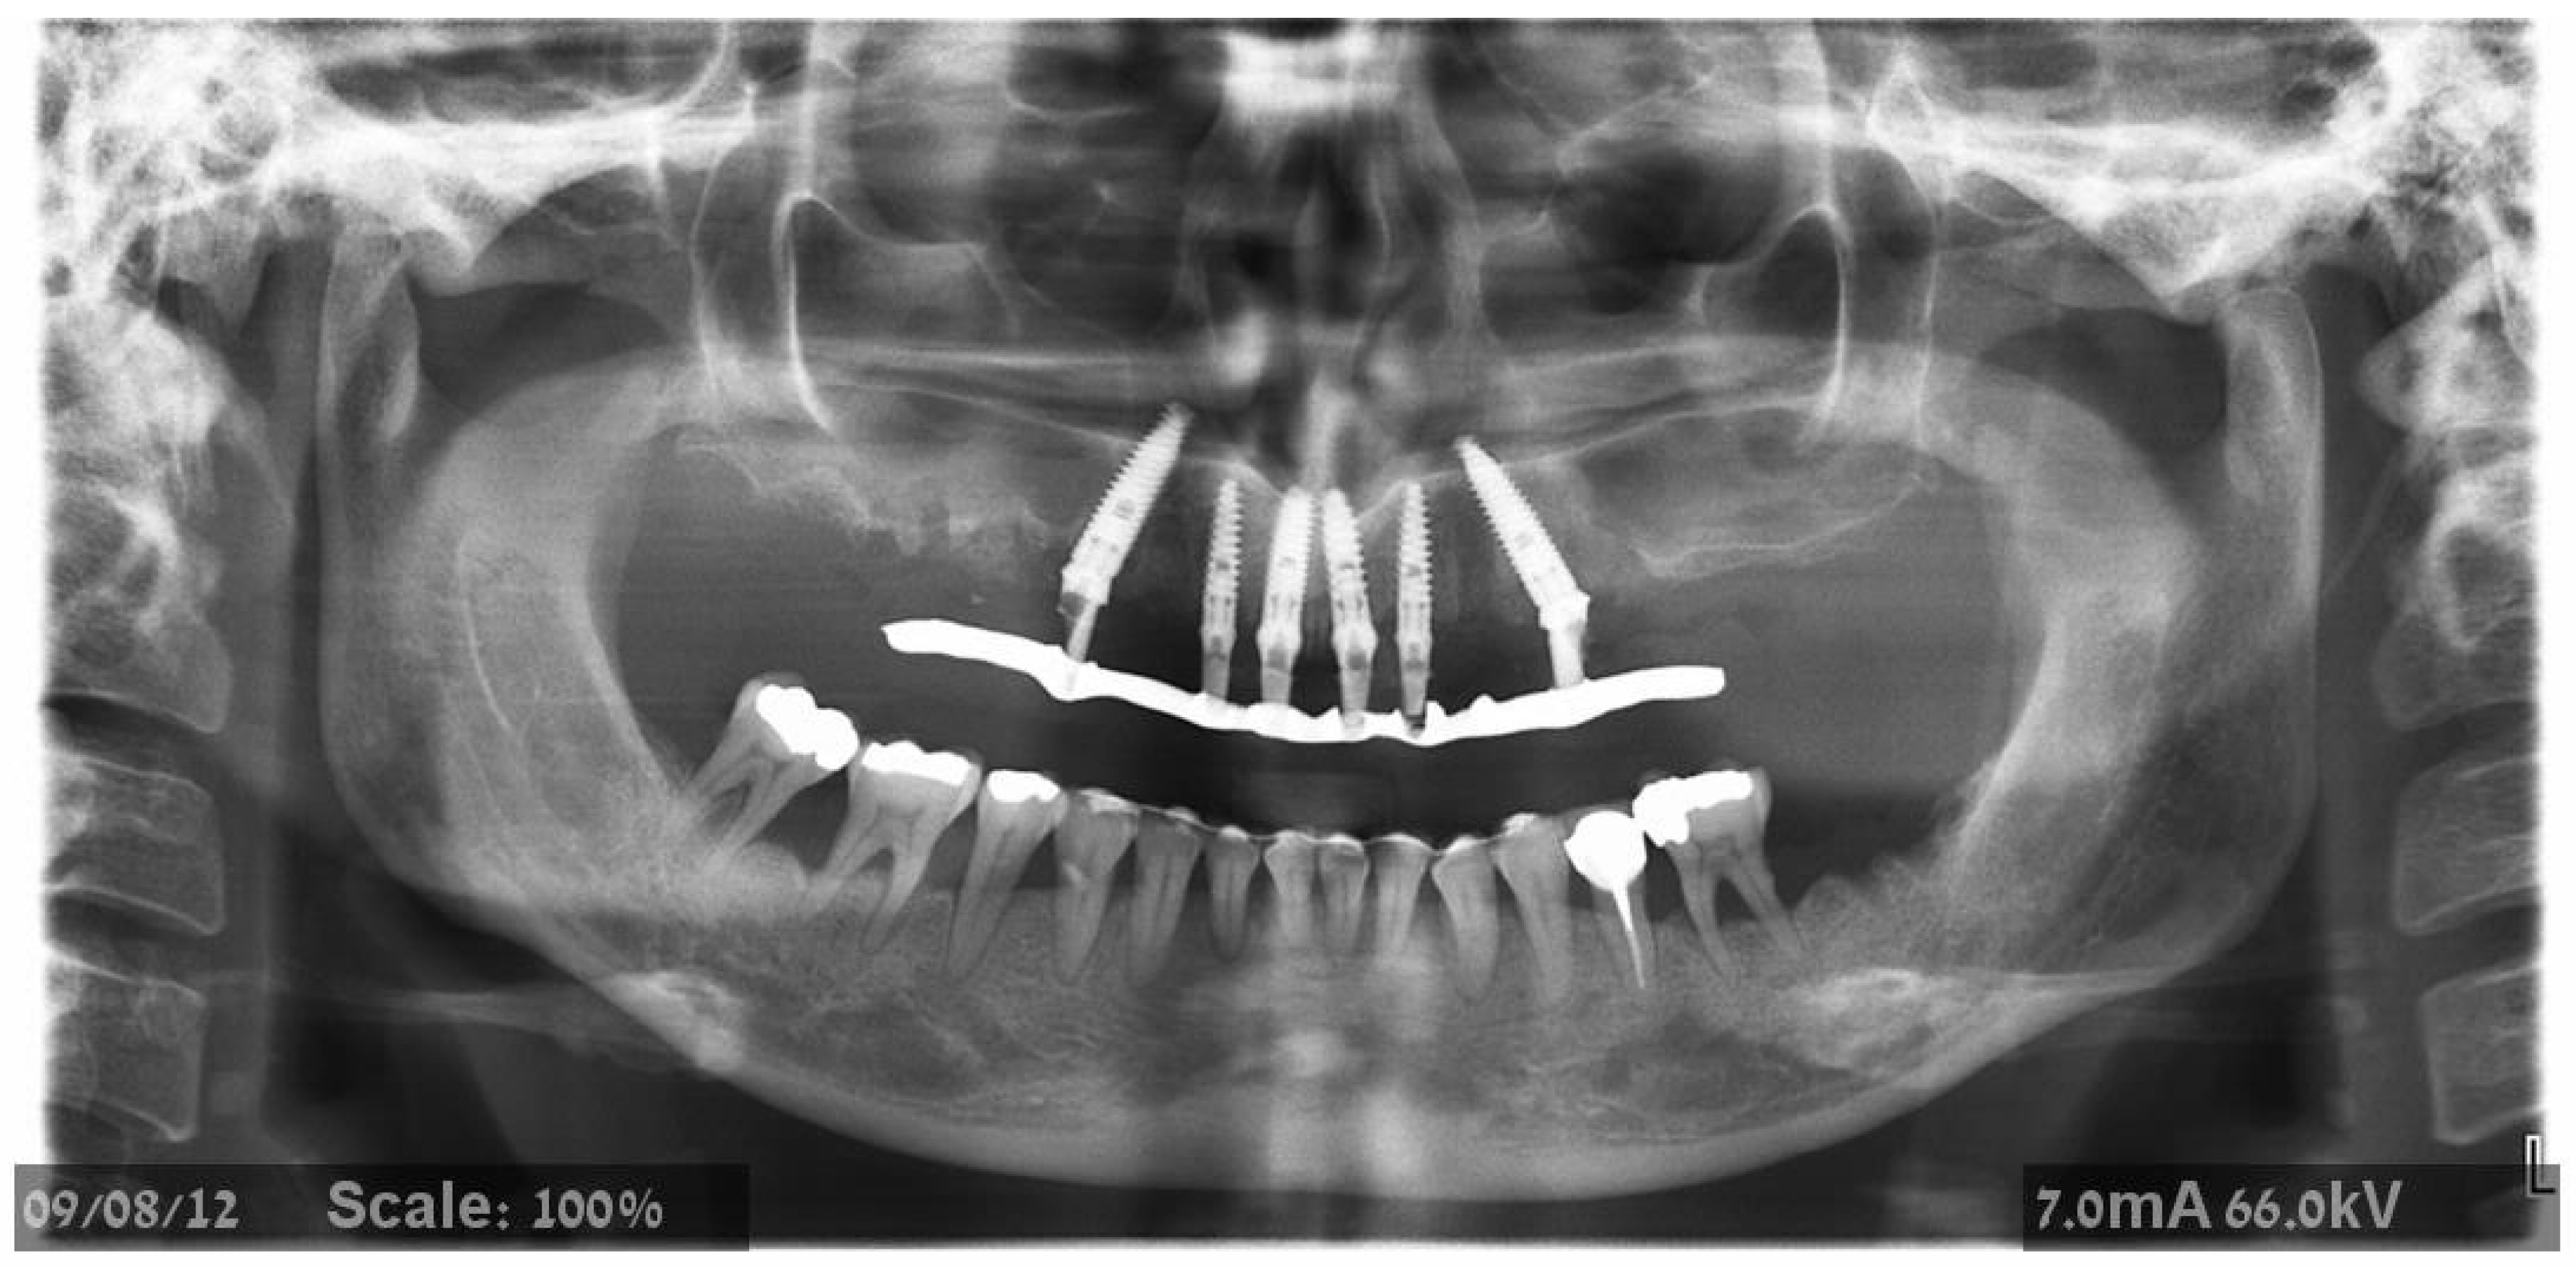

2.2. Surgical Treatment

2.3. Prosthetic Protocol